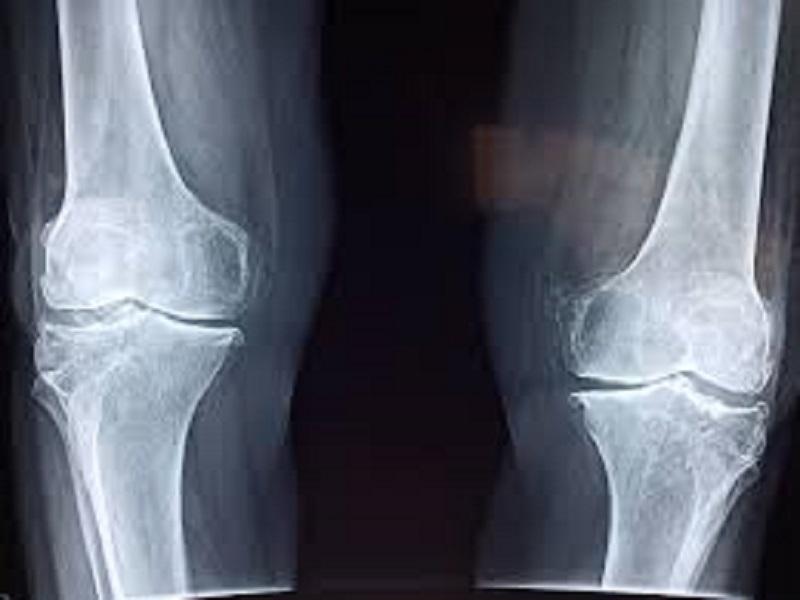

Alimentación adecuada y actividad física ayudan a tener huesos sanos Piedras Negras • Publicado en 2020-08-22 En la edad adulta incrementa el riesgo de sufrir fracturas debido a que la parte interna de los...